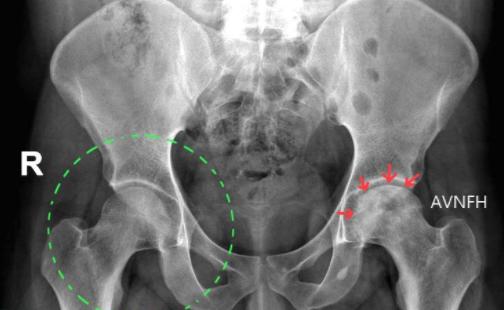

·青少年及小朋友须排除小儿股骨头缺血性坏死 (Legg-Calve-Perthes Disease)、 股骨头骨骺滑脱(Slipped Capital Femoral Epiphysis) 和骨骺炎(Apophysitis);耻骨骨炎(Osteitis Pubis)。

·有酗酒或是长时间使用类固醇的患者须排除股骨头缺血性坏死。

进一步的的影像检查如MRI,可排除髋关节唇的破裂、初期的股骨头缺血性坏死、滑囊炎、肌肉脓疡、腰椎椎间盘与神经压迫的情况。